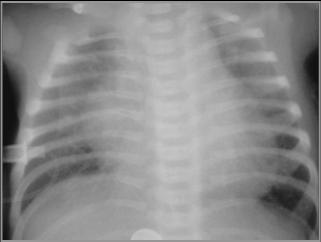

Hypoplastic Left Heart Syndrome